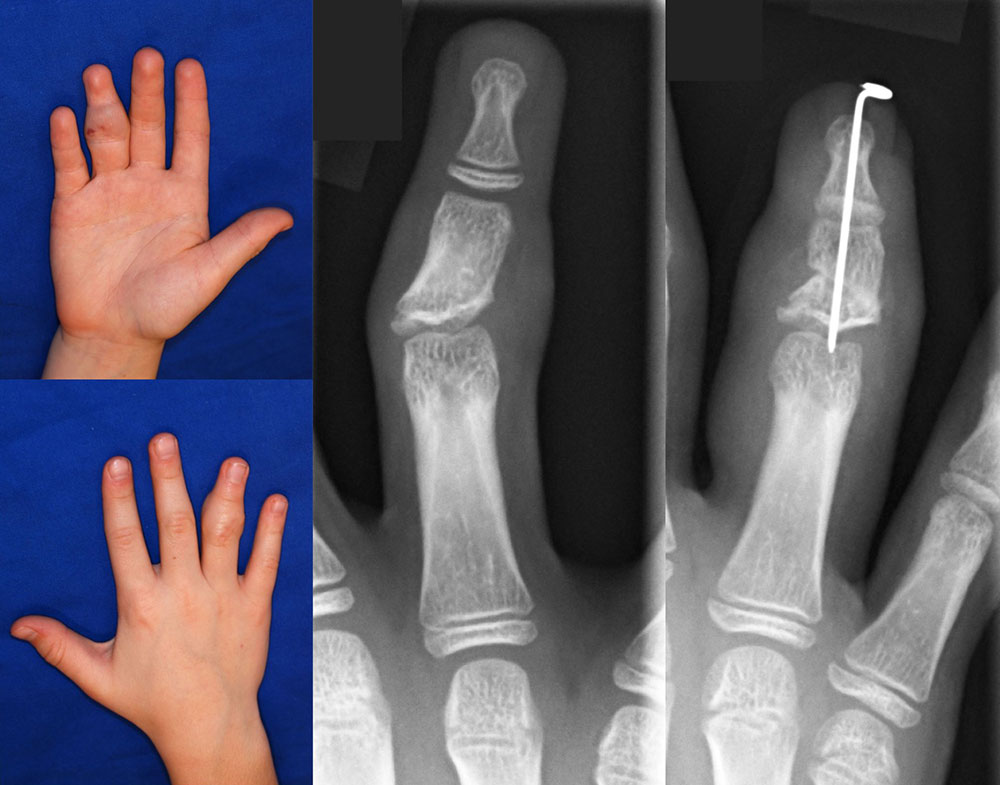

Venous malformations at a functionally important site

Circumscribed venous malformations at functionally important sites are difficult to treat. The VM in this two-year-old patient only extends to one part of the thumb, but the sensitive thumb pad is affected, which is important for grasping. In this case, ultrasound dissection has proven to be helpful. However, a recurrence within 15 months could not be prevented. A second ultrasound dissection is planned via a fish mouth incision with distalization of the excess skin and resection of the distal pad-like parts. A conceivable alternative would be resection of the entire thumb pad or interventional therapy. For reconstruction, the entire palmar distal phalanx would have to be replaced by a sensitive microvascular partial big toe transplant. Even after this complex therapy, recurrence is possible.